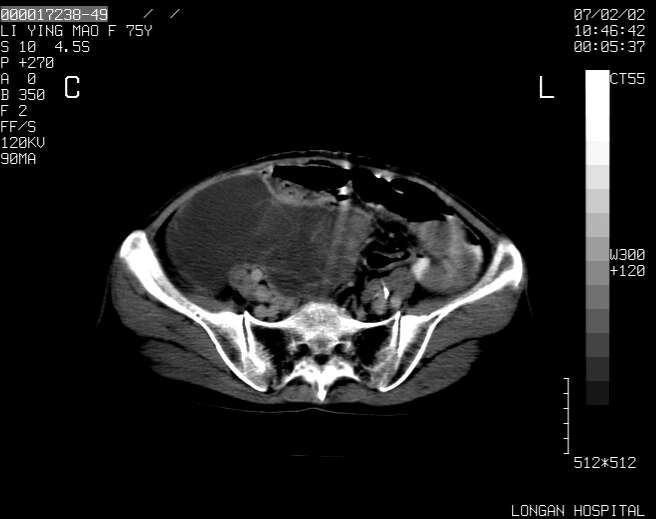

以下是引用dyqct在2007-2-10 8:53:00的发言:[br]考虑:1、肝脏多发囊肿[br] 2、左肾囊肿,右肾多发结石并积水。[br] 3、右胸少量积液。[br] 4、右肾周包裹性积液或淋巴管瘤(有见缝就钻的征象、薄隔、小结节状钙化)?[br] 5、腰椎动脉瘤样骨囊肿?[br] [br] [br]